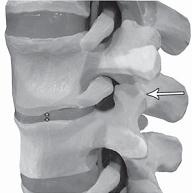

На фото № 6 макета позвоночника наблюдается смещение (подвывих) суставных поверхностей дугоотростчатых суставов. На фото № 7 наблюдается смещение (подвывих) суставных поверхностей дугоотростчатого сустава (увеличенный вариант). ![]() На фото № 8 макета позвоночника наблюдается перерастяжение дугоотростчатых суставов вследствие вытяжения. На фото № 9 наблюдается перерастяжение дугоотростчатого сустава (увеличенный вариант). ![]() Фото № 10 На фото № 10 макета позвоночника наблюдается нормальное взаимоотношение суставных поверхностей дугоотростчатых суставов, в норме высота межпозвонкового диска и межпозвонковых отверстий. ![]() Фото № 11 На фото № 11 макета позвоночника наблюдается смещение (подвывих) суставных поверхностей дугоотростчатых суставов. Подобное смещение, как правило, происходит вследствие развития дегенеративно-дистрофических процессов в межпозвонковом диске. При этом уменьшается высота диска, сужается просвет фораминального отверстия (межпозвонкового), что может способствовать ущемлению спинномозговых корешков (нервов) и сосудов. ![]() Фото № 12 На фото № 12 макета позвоночника наблюдается перерастяжение дугоотростчатого сустава вследствие вытяжения, расширение фораминального отверстия, а также растяжение задних отделов фиброзного кольца межпозвонкового диска и сближение вентральных (передних) отделов тел позвонков. Это приводит межпозвонковый диск в клиновидное состояние, что способствует выталкиванию содержимого межпозвонкового диска из передних его отделов в задние. |